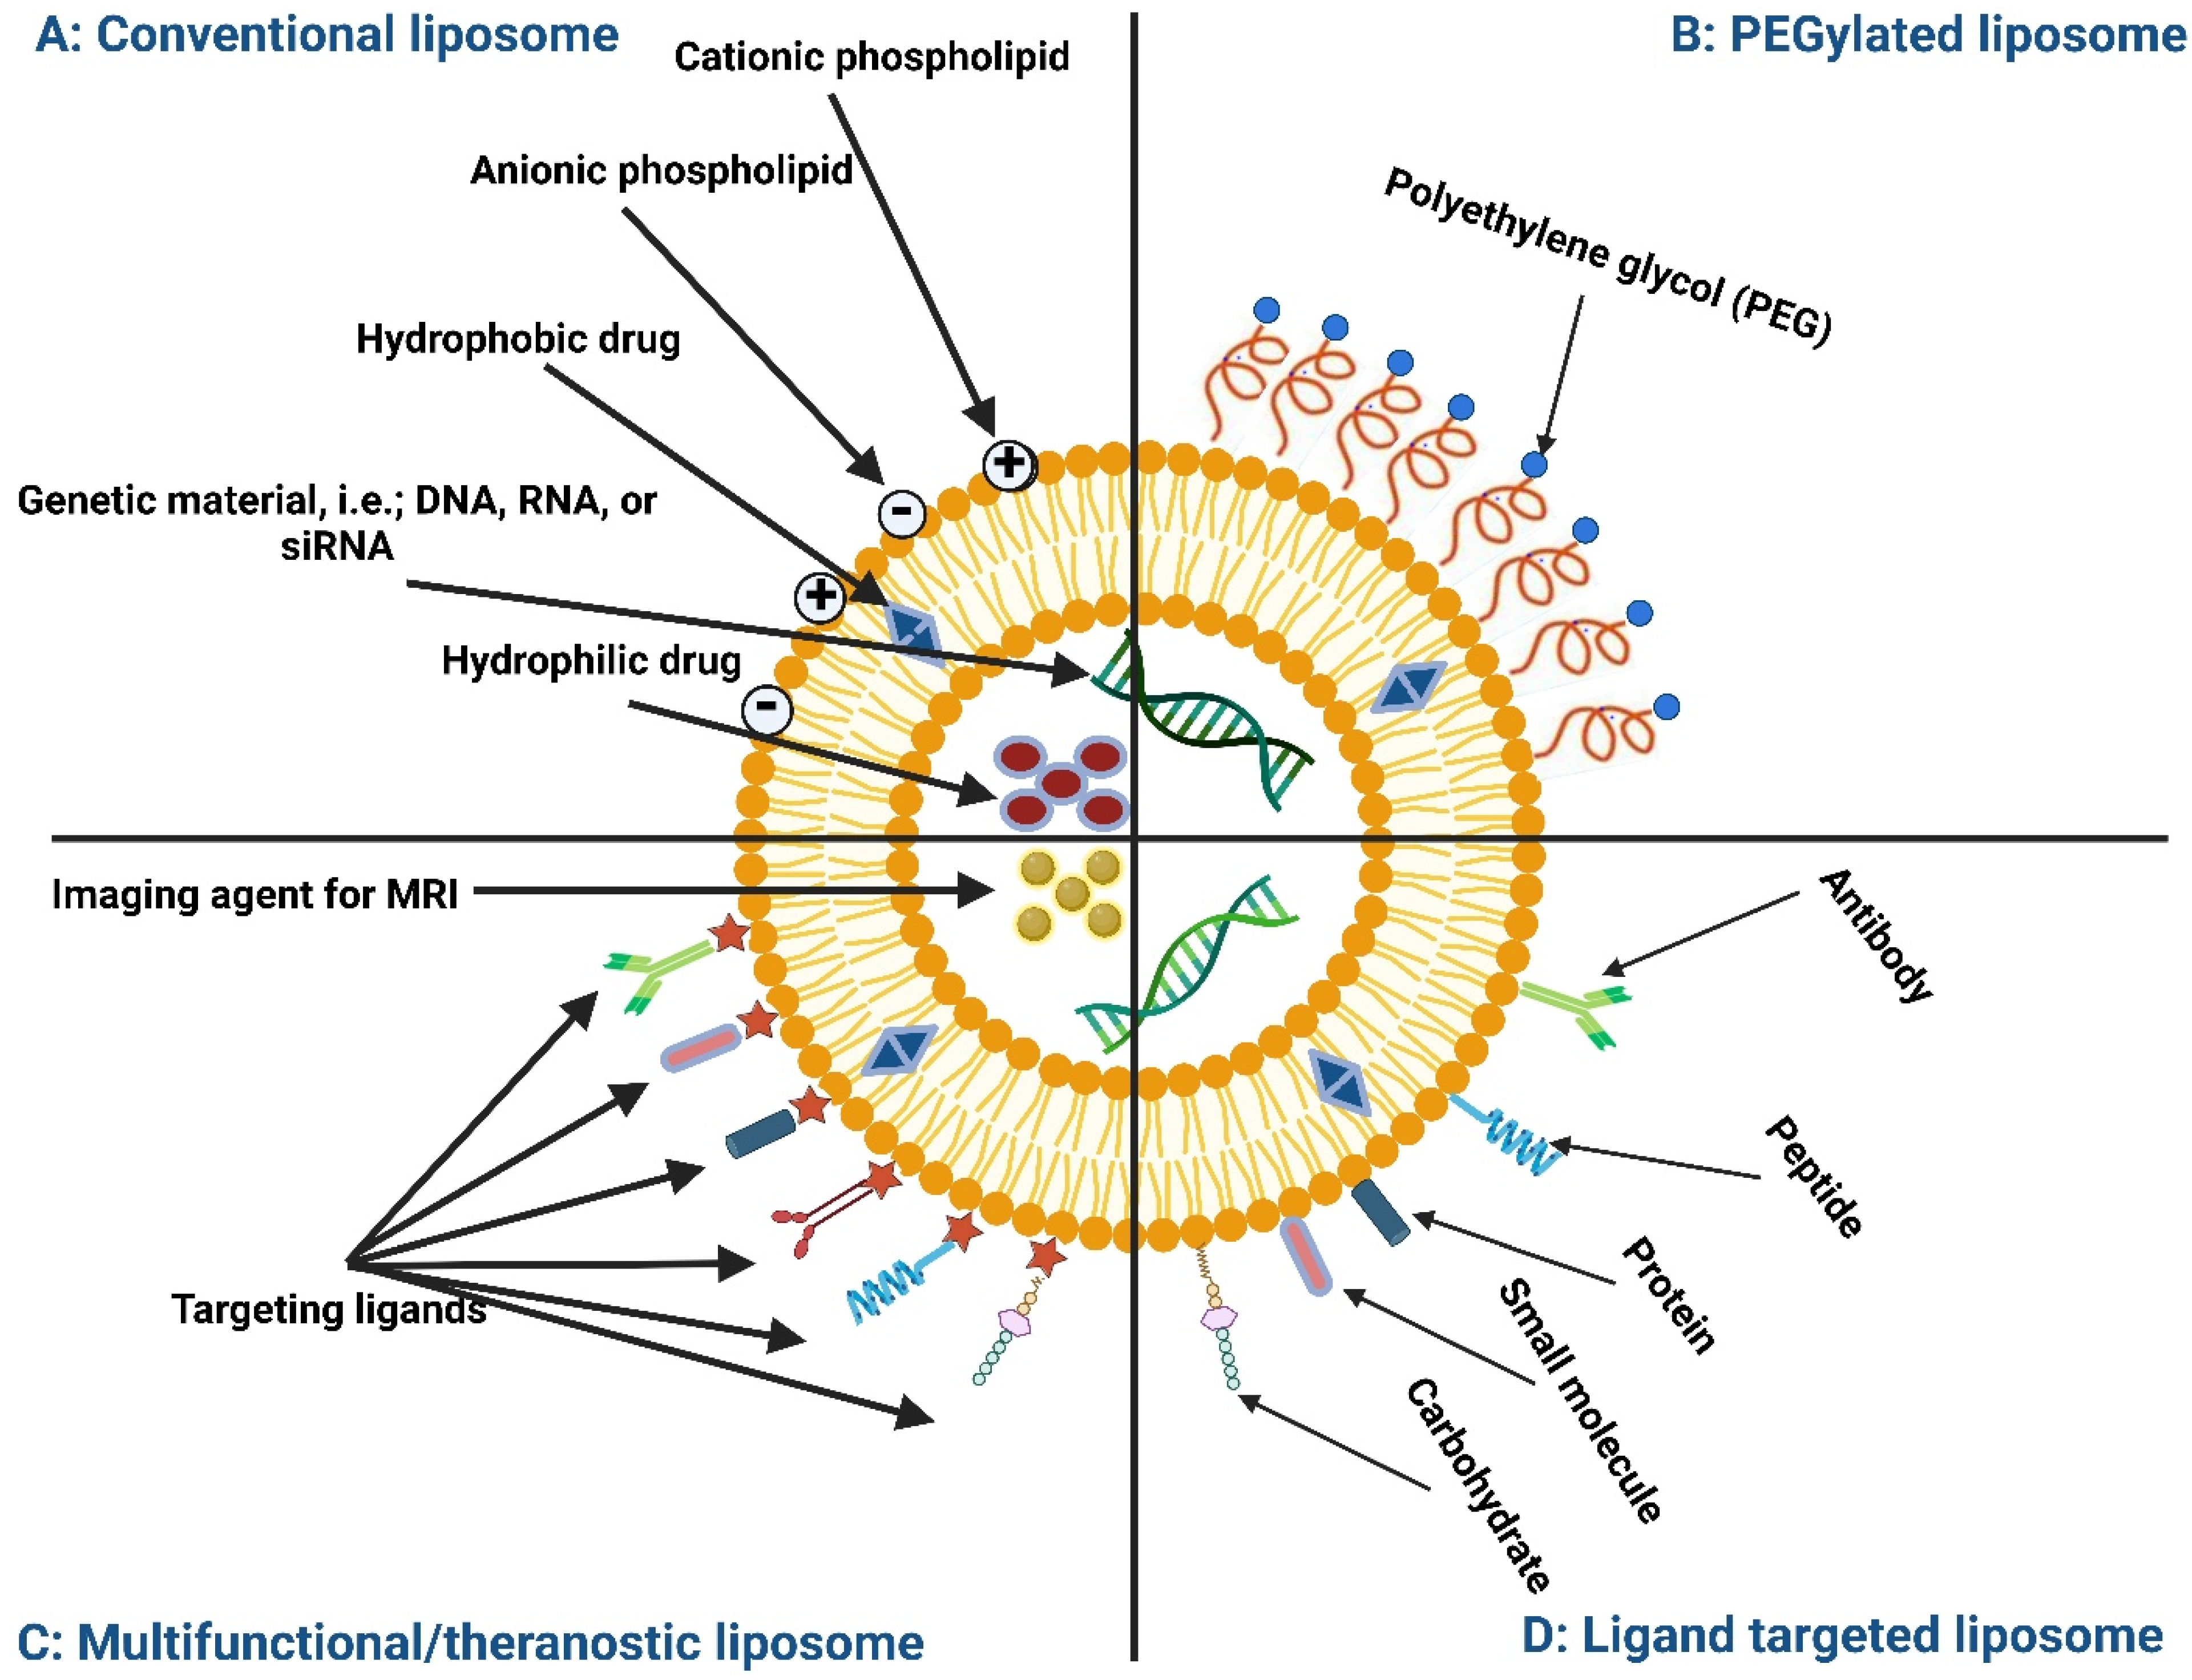

2. Structure and Composition of Liposomes and Extracellular Vesicles

2.1. Structure of Liposomes and Extracellular Vesicles

2.2. Lipid Composition

2.3. Protein Composition

2.4. Carbohydrate Composition

2.5. Polymer Composition